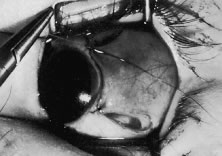

The tendon of the rectus muscle is elevated by lifting it away from the globe with the Jameson hook in a plane that is perpendicular to the surface of the globe. With gentle traction on the muscle insertion with the Jameson hook, a fine spatulated needle with a synthetic absorbable suture is woven through the tendon 1 mm from its insertion to the globe (Fig. 24). The needle exits at the superior edge of the muscle tendon and is then passed back underneath the tendon of the muscle (Fig. 25A and B). The needle is then passed back through the tendon from underneath (lock bite) and out the anterior surface of the tendon, taking a 2-mm portion of tendon that will be incorporated into the double-lock knot. Taking too large a lock bite will tend to narrow the width of the muscle tendon (Fig. 26A and B). The two sutures are brought up and held by the surgeon's thumb on the frets of the Jameson hook (Fig. 27). A blunt-tipped Westcott scissors is used to cut the muscle tendon free from its insertion. The cutting blade of the Westcott scissors is passed posterior to the muscle insertion. Care is taken not to push the tip of the scissor into the insertion but rather to pass the posterior tip of the scissor behind the muscle tendon, in the free space created by elevating the muscle with the Jameson hook. Two or three snips usually are required to remove the muscle from the globe. Care is taken to cut the scleral portion of the insertion flush with the globe. Leaving a large stump at the old insertion will leave a vertical white band of tissue that will show through the conjunctiva and leave an unsightly scar.

Fig. 24. A fine-wire spatulated needle is passed through the anterior insertion. Care is taken to pass the needle through the fibers of the tendon and not just the muscle capsule. The needle is passed back through the tendon from underneath to create a loop of suture. The loop will enable the surgeon to secure the tendon with a lock knot at the muscle insertion.

Fig. 25. A. Lock knot. A double-throw lock knot is secured at the superior and inferior pole of the tendon. B. Diagrammatic representation of the “double lock knot.”

Fig. 26. A. About 1 to 2 mm of tendon are incorporated in each lock bite (top).Too much of the tendon into the lock stitch will narrow the width of the muscle tendon (bottom). B. A narrowed insertion resulting by incorporating too much tendon in the lock bites.

Fig. 27. The surgeon holds the Jameson hook. The suture attached to the muscle insertion is pulled up and trapped between the surgeon's thumb and the frets on the hook. The assistant is exposes the upper pole of the muscle insertion with a Stevens' muscle hook so that the surgeon can cut the muscle tendon from the globe.

The muscle is suspended to verify that both the muscle tendon and the muscle capsule are incorporated with the suture and its lock bites (Fig. 28). In addition, pulling the sutures superior and inferior will assure the surgeon that the transverse suture that was woven through the tendon was not cut when the muscle was removed from the globe (Fig. 29).

Fig. 28. The surgeon suspends the rectus muscle to ensure that the muscle tissue is held securely by the sutures. This technique also will ensure that the transverse suture that was passed through the tendon has not been cut (A, B).

Fig. 29. A. After the muscle has been cut free from the globe, the surgeon should pull gently on the suture. This pull not only ensures that the suture is attached securely to the muscle but also tests whether the transverse portion of the suture placed through the tendon has been cut in the process of removing the muscle from the globe. B. When the transverse suture has been cut, an additional suture should be passed through the tendon so that the muscle will be held securely when it is recessed to its new insertion site.

The globe is stabilized with two locking Castroviejo forceps with 0.5-mm teeth (Fig. 30). Care is taken to grasp the most superior and most inferior portions (for vertical muscle, the most lateral and most nasal portions) of the insertion. For recessions, exposure of the sclera posterior to the insertion is obtained by abducting or adducting the globe while applying a gentle lifting action of the forceps at the insertion. This elevating, or proptosing the globe from the orbit, opens the edges of the conjunctival-Tenon's incision and provides improved exposure of the sclera where the muscle will be reattached.

Fig. 30. The globe is stabilized with two Castroviejo locking forceps. The forceps are held by the assistant. Inset. Magnified view of this forceps.

A Castroviejo caliper is used to mark a point on the sclera at a predetermined distance from the posterior portion of the muscle insertion (Fig. 31). Some surgeons prefer to mark the sclera the using the limbus as a reference point. These surgeons believe that it is more accurate to measure from the limbus than from the insertion of the rectus muscle because the insertion may have some anatomic variation. If a large recession procedure will be performed, measurement from the limbus will introduce a cord effect that will increase the amount of recession achieved (Fig. 32). To reduce this effect, William Scott has designed a curved ruler that provides a more accurate measurement of the arc. It is important for the surgeon to be careful and consistent with the measurement technique so that the effect of the surgical procedures can be critically evaluated.

Fig. 31. A. The assistant provides exposure and stabilizes the globe with the Castroviejo forceps. A Stevens' hook is used to retract the conjunctiva. The surgeon marks the sclera, taking care to make the marks directly posterior to the old insertion. B. The surgeon makes final confirmation on the number of millimeters that the caliper is set on.

Fig. 32. When recessions are large, a Castroviejo caliper is used to measure a cord and not the distance along the scleral surface. For small recessions, these effects are negligible. For large recessions, or when measurements are taken from the limbus, this technique can introduce an error in measurement.